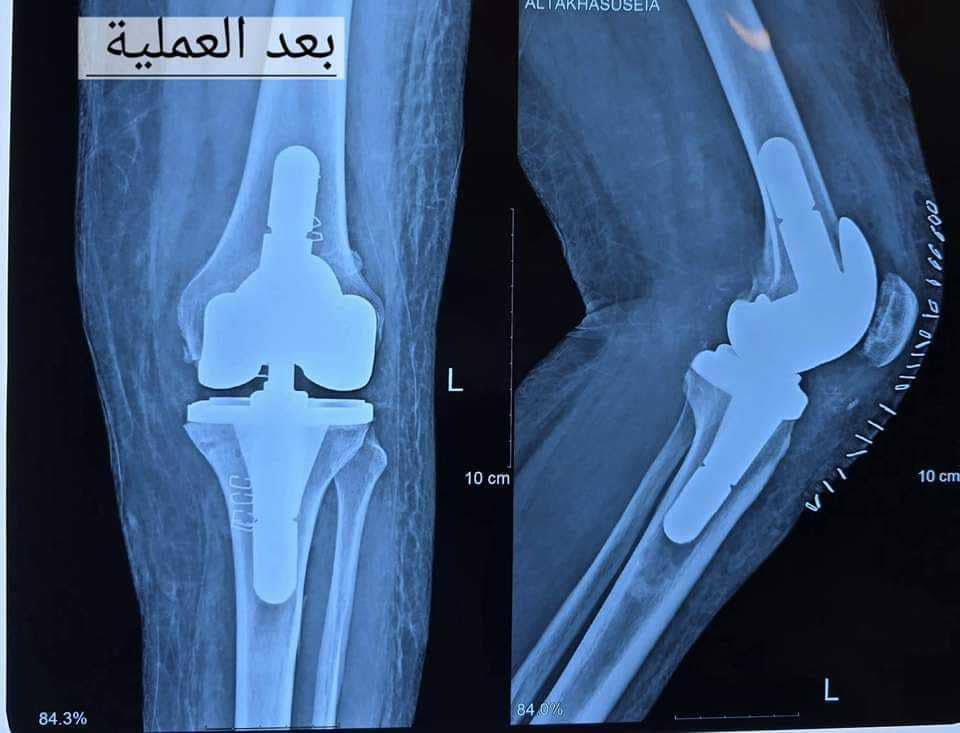

أجرى فريق طبي في مستشفى الديوانية التعليمي، اليوم السبت، عملية نوعية لتبديل مفصل الركبة الكامل من النوع المعقد، لمريضة من أهالي المحافظة.

وأوضح رئيس الفريق الطبي الطبيب الاختصاص، الدكتور نداء الوائلي، بحسب بيان صادر عن وزارة الصحة، وتلقت “النعيم نيوز” نسخة منه، أن “المريضة كانت تعاني من روماتيز المفاصل، مع هشاشة العظام، وعدم استقرارية في مفصل الركبة”.

وأكد، أن “عملية تبديل المفصل بالكامل تكللت بالنجاح، والمريضة بصحة جيدة، بجهود الملاكات الصحية والطبية والتمريضية في المستشفى”.

ووفقاً للبيان، فإن “هذا النوع من المفاصل يعد من الأنواع المعقدة الأمريكي المنشأ الذي وفرته وزارة الصحة، بعد أن كان المواطن العراقي، يجري مثل هذه العمليات خارج العراق”.